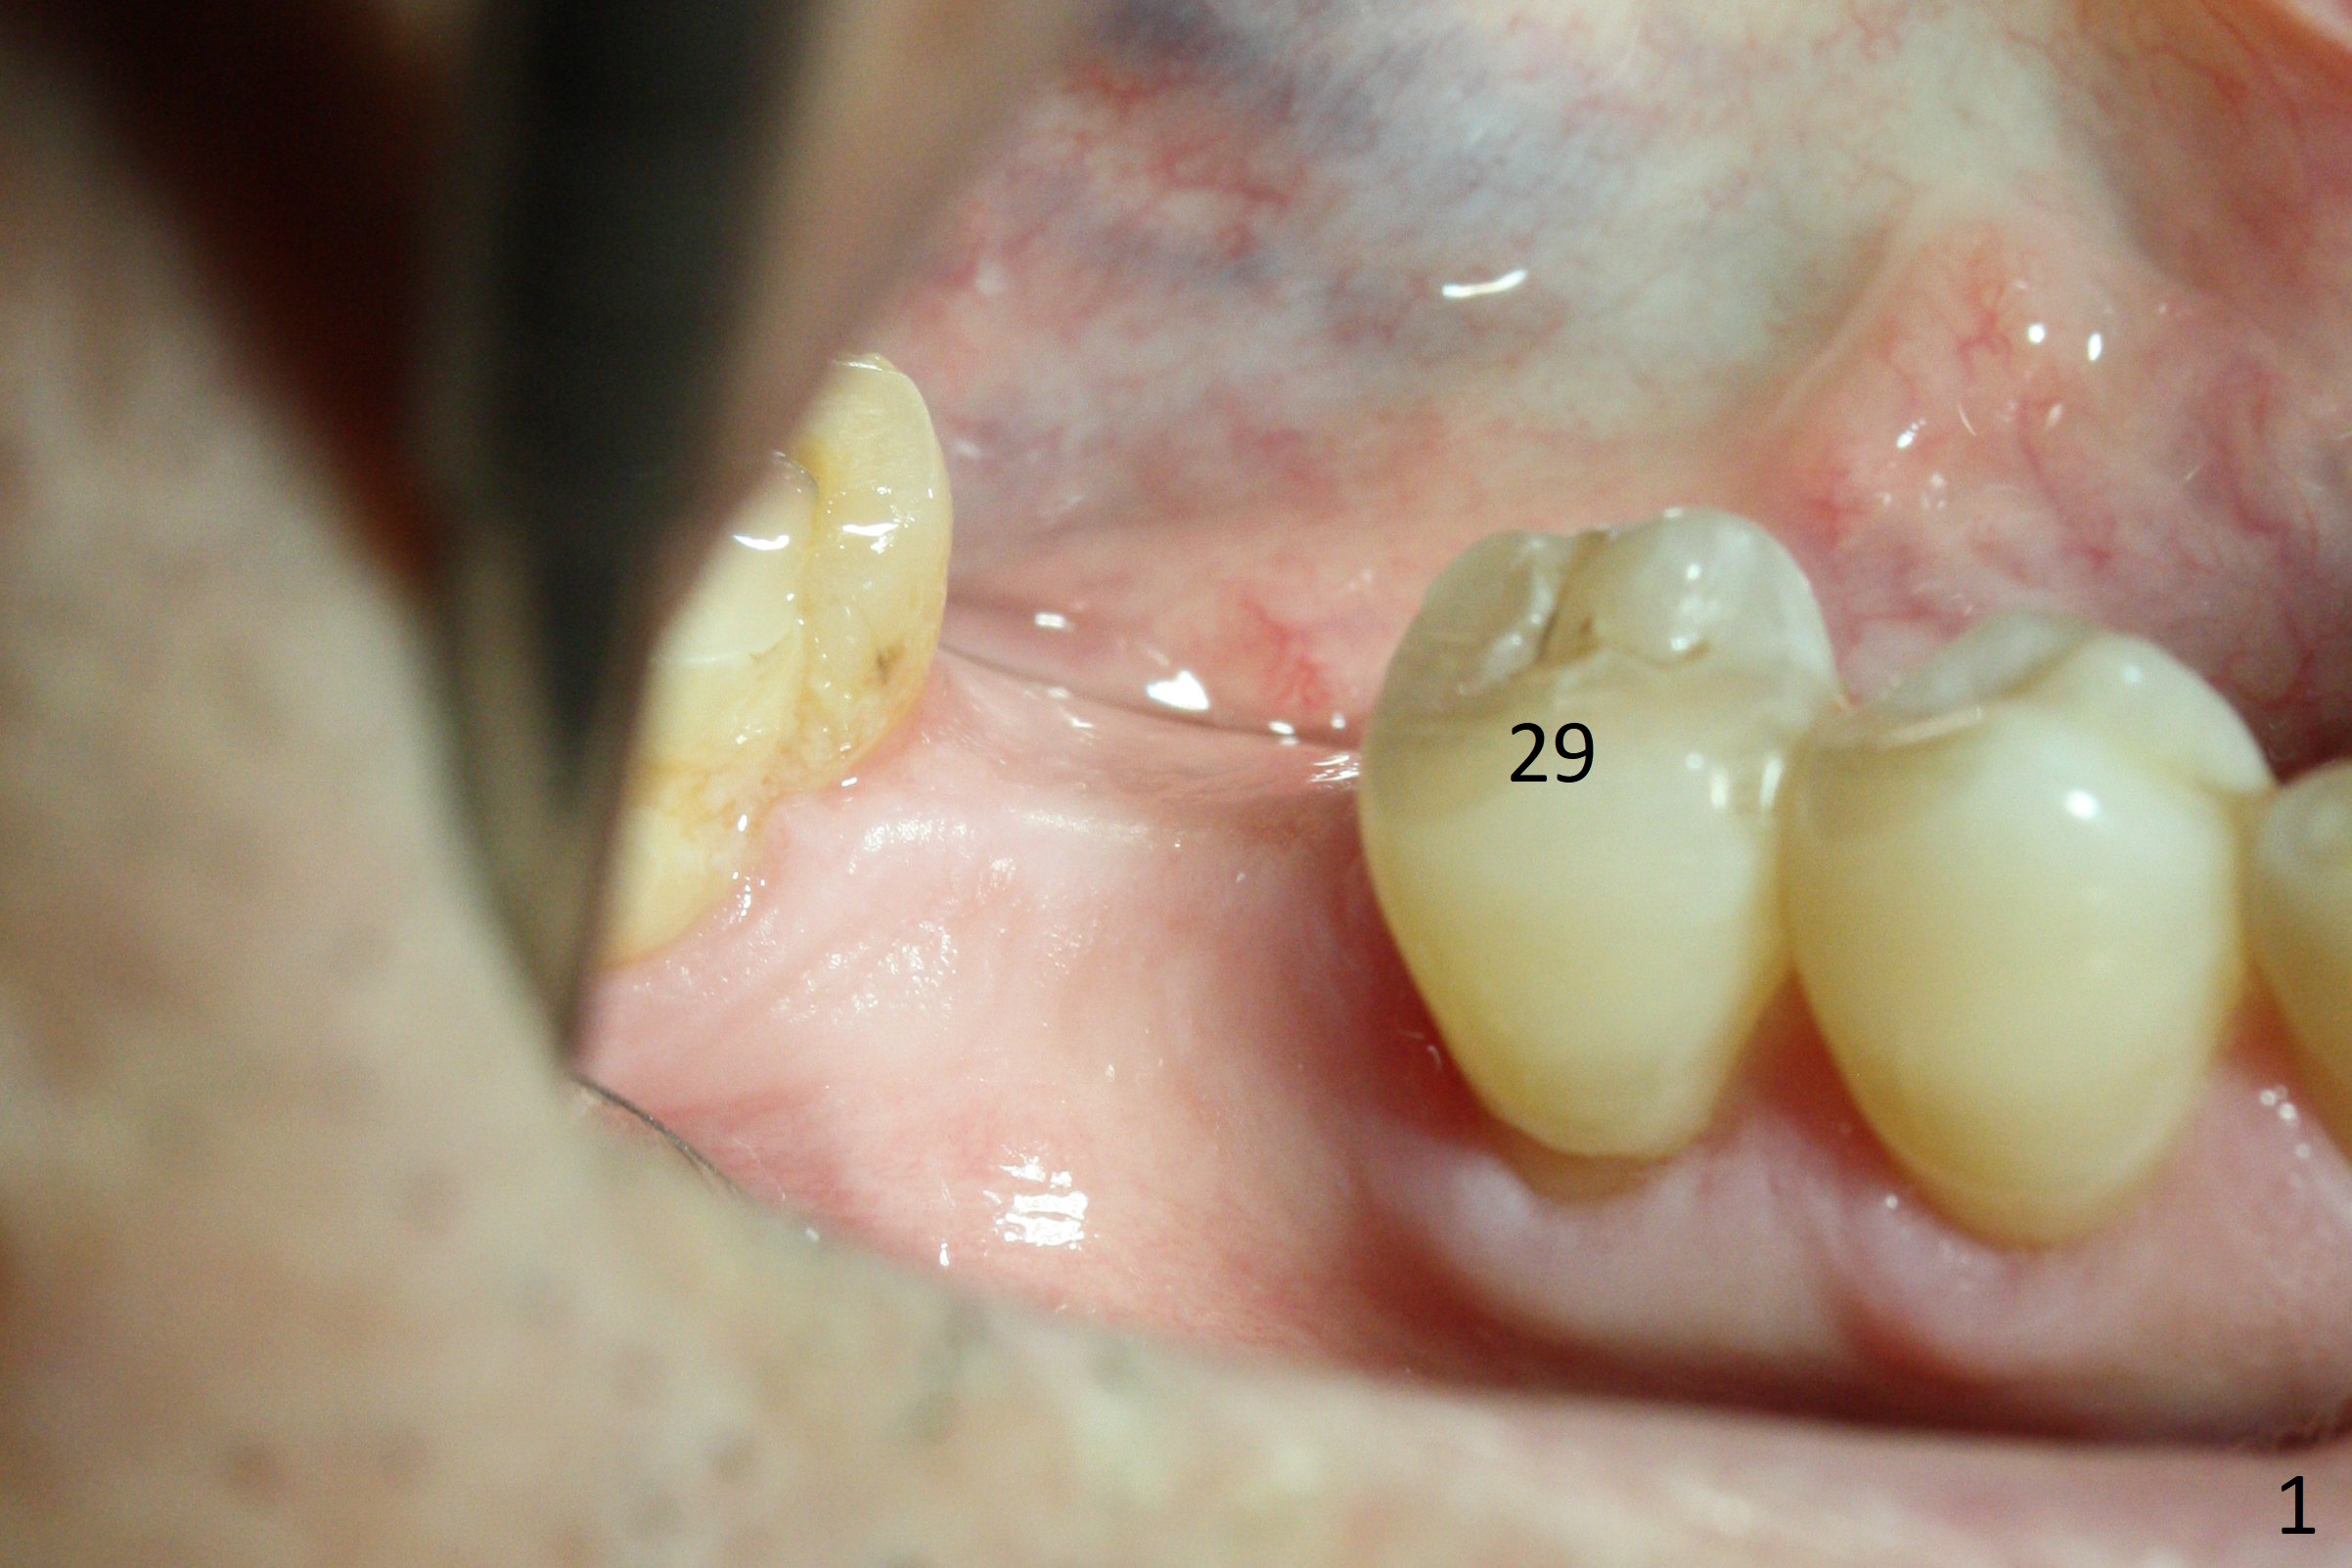

A 51-year-old man has a pyramidal ridge at #30 (Fig.1) with mild supraeruption of the opposing tooth (Fig.2 arrow). Ridge reduction will be done (Fig.3 red curved lines) prior to Bicon implant placement (green). A healing abutment is to be placed, followed by periodontal dressing.